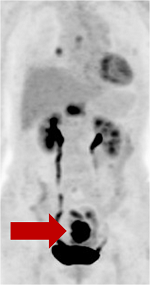

6. Positron emission tomography(PET)

머리부터 발끝까지 몸 전체에서 비정상적인 활성을 가진 세포를 선별하는 검사로 주로 진행성 위암환자에서 림프절 전이나 원격전이여부를 판단하거나 재발을 진단할 때 주로 사용된다. (CT와 PET은 동시에 처방할 수 없고 CT에서 림프절 전이의 소견이 있다는 것을 확인 한 후에 PET를 시행이 가능하다)